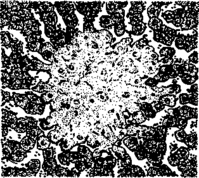

Сальмонеллезная гранулема в печени теленка

Гранулемы (паратифозные узелки) имеют вид очажков размножающихся ретикулоэндотелиальных элементов, расположенных по ходу капилляров. Клетки гранулем со светлыми крупными ядрами обладают способностью к фагоцитозу. Кроме печени и селезенки паратифозные узелки отмечают также в почках, лимфатических узлах, костном мозге. В печени и реже в других органах можно наблюдать образование очаговых эндофлебитов, но они не патогномоничны для сальмонеллеза.